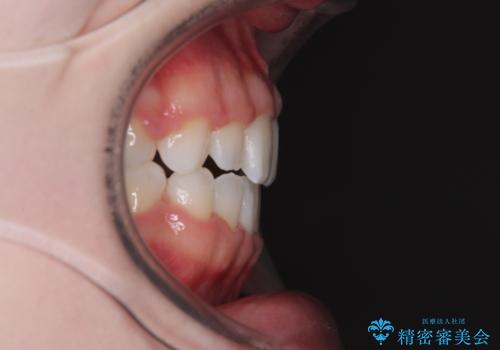

舌の突出癖により上下前歯は接触できず、更には前方に押し出されて出っ歯になっている状態でした。

上下左右の第一小臼歯4本を抜歯し、ワイヤー装置での抜歯矯正を行っていくのですが、原因である舌の突出癖を改善しないことには治療がうまく進められないため、舌のトレーニングを徹底するよう指導していくこととしました。